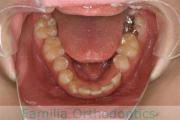

- ≫治療後

二期治療開始前は叢生(でこぼこ、凹凸、ガタガタ)がかなりありましたので、保定をしっかりしないと段差ができてきたり後戻りのリスクがあります。

上顎

下顎

前歯の関係など

右側

正面

左側